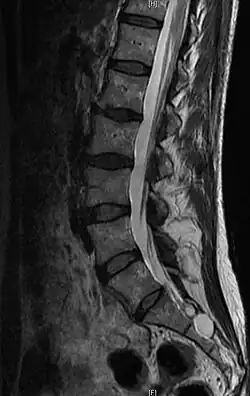

Torbiel Tarlova (ang. Tarlov cyst, perineural cyst) – wrodzona zmiana torbielowata o niejasnym pochodzeniu, lokalizująca się między onerwiem a zewnętrzną blaszką opony miękkiej obejmujących zwój nerwowy rdzeniowy. Włókna nerwowe przebiegają w ścianie torbieli.

Torbiele Tarlova rozpoznawane są zazwyczaj przypadkowo w badaniu MRI wykonanym z innego powodu, np. zmian zwyrodnieniowych kręgosłupa.